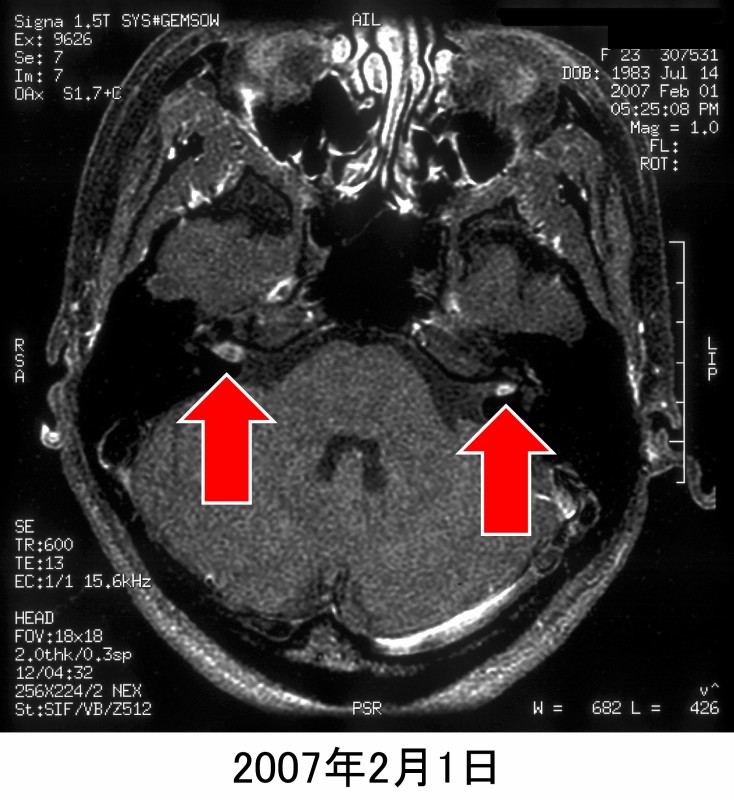

しかし造影MRI(図12)にて、両側内耳道に腫瘍が観察されます。腫瘍発見後は東北大学耳鼻科にて経過観察となっています。